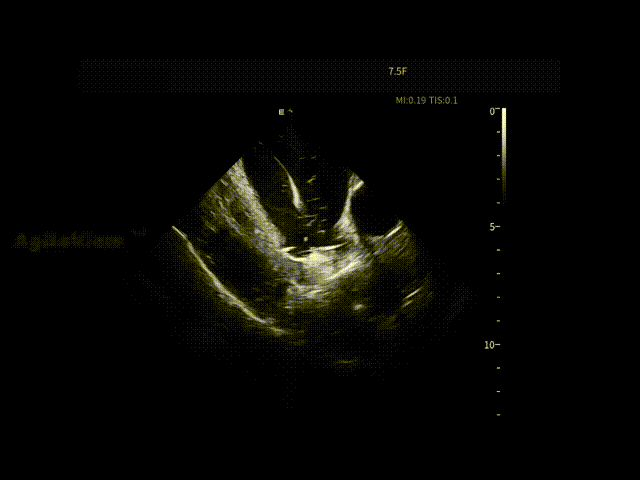

在肺静脉隔离及左房后壁相关操作过程中,ICE持续显示消融导管与心房组织之间的空间关系与贴靠状态,使每一次能量释放都建立在明确的影像反馈之上,减少反复调整,提升操作连贯性。

导管形变与贴靠-LA后壁

导管形变与贴靠-LIPV

导管形变与贴靠-LSPV

导管形变与贴靠-RIPV

导管形变与贴靠-RSPV

LPV口部消融

LPV前庭消融